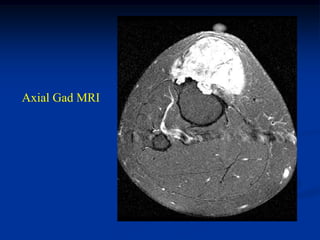

Case # 124.1                    AP and lat x-ray

50 year male with chondromyxoid fibroma proximal

tibia with 6 months of a tender tumor mass anterior tibia

Coronal T-1 MRI

Coronal PD FS MRI

Axial PD FS MRI

Axial Gad MRI